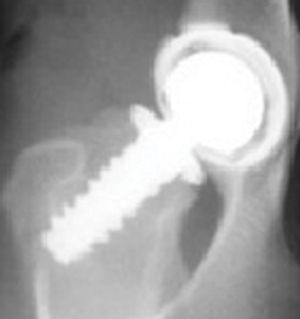

CHD has been called inherited, a developmental disease, and most accurately in the author's opinion, a "moderately heritable disease". CHD is a multifactorial disease with part of its cause being from genetic influences (estimated at 25%-80%) and part from environmental influences.